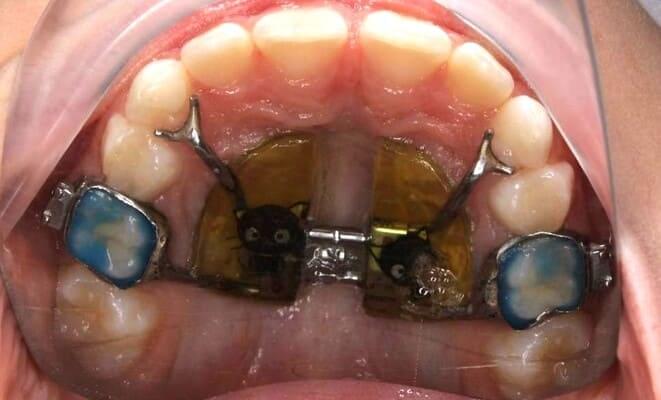

Ортодонтичне лікування незнімною апаратурою. Алєксєєва Аліна.

Дівчинка 9 років мала звуження верхньої щелепи, інфантильний тип ковтання (прокладає язик між зубів) та шкідлива звичка у вигляді смоктання пальця. Провели розширення за допомогою апарату Марко-Роса та усунули всі шкідливі звички, що призвело до чудового результату. Тепер зубо-щелепна система може гармонійно розвиватись, що дозволить

Ортодонтичне лікування незнімною апаратурою. Алєксєєва Аліна.

Часто батьки сумніваються відносно доцільності розширення щелеп для створення місця для повноцінного прорізування постійних зубів. Даний клінічний випадок – це та ситуація, коли правильна тактика у відповідному віці дає чудовий результат. Скоригували скученість зубів без брекет-системи. Апарат створив місце і зубки самостійно встали у правильне положення.

Ортодонтичне лікування незнімною апаратурою. Алєксєєва Аліна.

Хлопчик 8 років

Звуження верхньої щелепи, інфантильний тип ковтання та смоктання пальця призвели до формування відкритого прикусу. За допомогою апарату Марко Роса та додаткових елементів в ньому, досягли такого чудового результату.

Ортодонтичне лікування незнімною апаратурою. Алєксєєва Аліна.

Хлопичк 8 років

Звуження верхньої щелепи,інфантильний тип ковтання та дефіцит місця для постійних зубів

Отримали гарний результат за допомогою лише розширення на Марко Роса

Ортодонтичне лікування незнімною апаратурою. Алєксєєва Аліна.

Дівчинка 8 років

Було скупчення зубів на верхній щелепі через дефіцит місця,провели розширення на Марко Роса і досягли чудового результату без брекет системи

Ортодонтичне лікування незнімною апаратурою. Алєксєєва Аліна.

Хлопичк 8 років

Звуження верхньої щелепи,великий дефіцит місця для постійних зубів. Провели розширення на апараті Марко-Роса

Ортодонтичне лікування незнімною апаратурою. Алєксєєва Аліна.

Хлопичк 9 років

Великий дефіцит місця для прорізування постійних зубів,скупчення. Провели перший етап лікування- розширення верхньої щелепи за допомогою апарата Марко-Роса